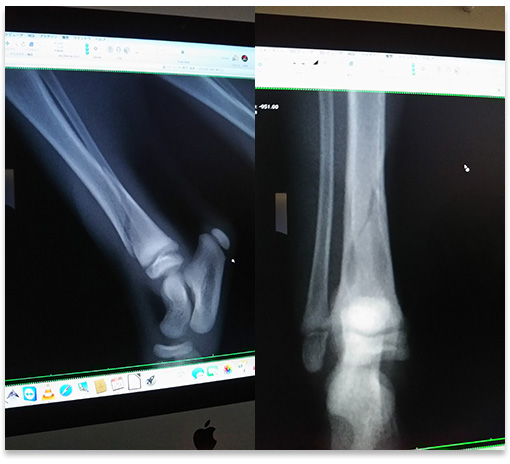

海男が右後ろ脚を骨折しました。

70cmほどの高さの所から脚を踏み外して落ちてしまい、落ちた途端に”ギャー!”と悲鳴をあげました。 すぐに歩けるか確認したけど、脚をつけると痛いようで”ギャー!”と悲鳴をあげるのですぐに通院。 レントゲン撮影して人間の脚に例えるとスネの辺りが骨折していました。 獣医の見立てではひどい骨折ではなく一ヵ月程度安静にしていれば良いとの事。 痛み止めの注射を打ってもらい、明後日再度レントゲンを撮影してひどくなっているようだったらギブスをする事になりました。 獣医から歩き回ったりしないように、通院に使っているキャリーケースで過ごさせるように言われたので、使っているトイレが入らないのでちょうど良さそうな大きさの段ボール箱をトイレに改造して、大きめのキャリーケースがあるでそのケースでしばらく過ごしてもらう事にしました。 もうちょっと注意していれば防げた事故だったのでとっても後悔しています。 帰宅してから罪悪感と脱力感で体が重く、とにかく後悔ばかりです。 今日は骨折する前までの離乳食は全て自分で食べて完食してくれたので、もう少しご飯の量を増やそうと嬉しく思っていた矢先の事だったので残念でなりません… 海男に申し訳ない事をしてしまいました。 帰宅するとなつが心配そうに保護した当時のように海男のそばに付きっきりでいました。 今まで骨折した動物は今いる猫のパンダくんと先代犬のラム、現在庭を縄張りにしているノラ猫のおんぢくんが骨折経験あり。 パンダくんは当時ノラ猫で、交通事故なのか幼稚園で仕掛けた捕獲器の罠の扉が挟まったのか骨盤が骨折。 動けなくなっていた場所を考慮すると幼稚園が怪しい。 二週間近く入院してある程度歩けるようになるまで二カ月ほどかかった。 現在は問題なく歩けるようになったけど、正常な猫のように体を丸める事ができなく後ろ脚で顎や耳の辺りが痒くて掻こうとしても脚が届かなく掻く事ができません。 掻こうとする仕草を見つけた場合は痒そうな所を掻いてあげています。 老後筋力が落ちてきた時は歩けなくなりそうな感じです。 先代犬のラムは交通事故で脚を骨折。 姉が運転する車に轢かれました… それ以来姉を見ると唸ってました。 入院せず自宅療養で、もう20年くらい前の出来事なのでどのくらいの期間安静にしていたのか忘れました。 その後は市内の国立公園の山以外はほとんど踏破するまでの登山犬に成長。 市内の山と言っても南アルプスなどの山々がある登山愛好家には恵まれた市になるので、その辺の低山の山とはちょっと違います。 おんぢくんは庭に現れる前から顎を骨折していたようで、去勢手術のため捕獲して手術した病院ではノラ猫のためなのか何も言われず当然処置もしてくれず、その後歯槽膿漏で診察のため通院した病院で顎の骨が折れていると言われ判明。 庭に現れた時からいつも口を半開きにしていたのでヘンだなと思っていたけど、まさか顎の骨が折れているとは思いませんでした。 顎がずれているので噛み合わせがかなり悪く硬い物はあまり食べれません。 骨折してから長い時間経過しているので、治すには再度顎の骨を折らないとならないと言われ、食事もできているのでこのまま様子をみましょうと言われ現在に至ります。 骨折した時はかなり痛かったでしょうね… 痛みが治まるまで何も食べずにジッと辛抱していたのでしょう。 そんな事を思うと、その後うちにやってきてくれて本当に良かったです。 海男の場合はどのくらい回復するかわからないけど、明日里親さんに骨折の事を連絡しないとです。 もし断られたら再度里親さんを探さないとなりません。 でもいまだに里親さんとは直接連絡を取った事がないんですよ… なので正確には間に入ってくれた同級生のお母さんに連絡です。 診療代 7,340円 明細 再診料 540円 レントゲン検査(後肢)1セット 5,180円 レントゲン検査(追加) 1,620円 痛み止めの注射はおまけしてくれたようです。 レントゲンの写真。 ・ミルク&離乳食を飲んで食べた量(ミルクは注射器の目盛りから推定) 06:30 ミルク:13.0ml ミルクのみ 09:40 離乳食:37g 自力で完食 15:00 離乳食:38g ほぼ自力で完食 20:30 離乳食:ほとんど食べず 二、三口しか自力で食べず、その後口を開けて食べさせるが吐き出す 23:50 ミルク:12.0ml ミルクのみ (20時台の離乳食をほとんど食べなかったのでいつもより早めにあげた) 合計 ミルク:25ml 離乳食:80gくらい 体重874g PR コメントを投稿する